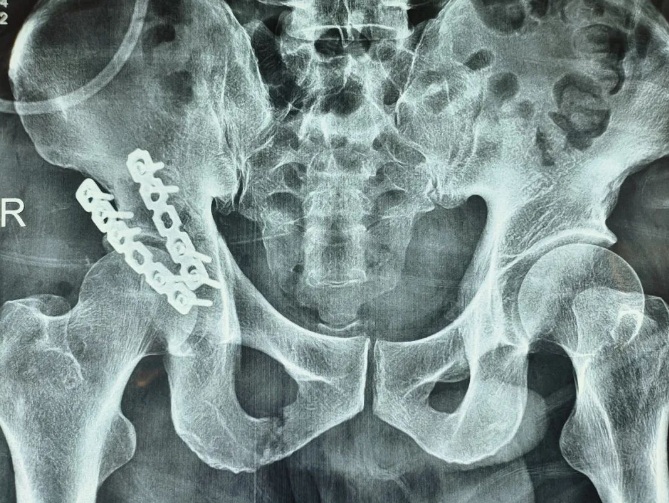

患者术后影像

业务院长韦向荣组织成立救治小组,针对该患者复杂的情况制定精细的手术计划,经过周密的术前准备,韦院长带领脊柱骨盆诊疗小组,历经近2个小时,顺利为患者进行了高质量的右侧髋关节脱位合并髋臼骨折切开复位内固定术,目前患者恢复良好正在积极康复中。